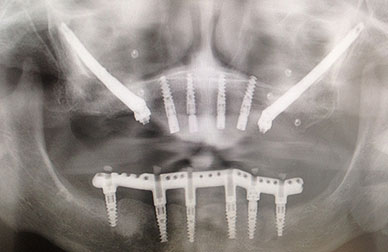

Implantes zigomáticos anclados en huesos más lejanos

Implantología avanzada